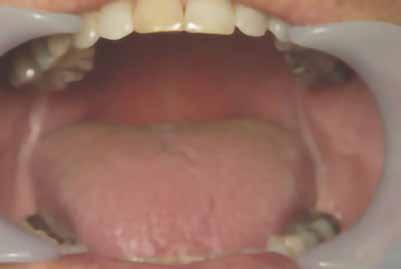

1. ábra: Nyelv helyzete az okkluzális sík felett.

2. ábra: Mallampati besorolás 4, mindegyik minimális orális térfogatot jelez.

angiotenzin II receptor antagonista) 50 mg naponta egyszer, Nexium (protonpumpa-gátló, amely csökkenti a gyomorban termelődő sav mennyiségét) (GERD) 40 mg naponta, Intuniv (multivitamin) 4 mg naponta, és aszpirin 81 mg naponta egyszer. Klinikailag a nyelv az okkluzális sík fölött helyezkedett el, hiperkeratózis (B), a nyelv légutakba való behúzódása és Mallampati 4, amely mind minimális szájüregi térfogatra utalt (1–2. ábra). Ezek indikálták az alvásfogászati készülékes kezelést. Az izomtapintás elhanyagolható volt, és az állkapocs mozgástartománya is normális volt. A maximális nyitás 45 mm volt (1–2. ábra), oldalirányú elmozdulással 12, illetve 10 mm balra és jobbra. Az állkapocs normál mozgástartománya 42–52 mm volt maximális nyitás esetén, emellett oldalirányú elmozdulás 14 mm volt [13]. Az állkapocs ízületeinek dinamikus funkcióértékelését Joint Vibration Analysis (JVA [BioResearch]) segítségével végezték, és a lágy szövetek esetében a normál határokon belülinek, valamint kétoldali porckorongok perforációjának mentesnek találták (3. ábra)